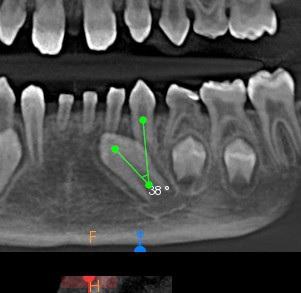

W żuchwie:

71,72,81 – zęby mleczne, wierzchołki korzeni skrócone.

Wykazują cechy resorpcji fizjologicznej.

81 71